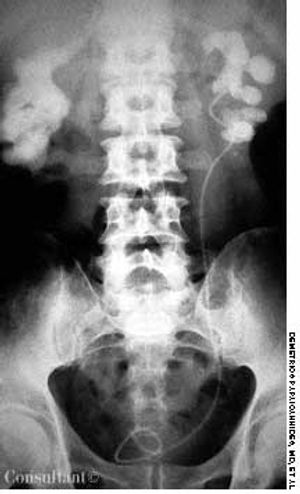

A 67-year-old woman was admitted to the hospital with fever, chills, unilateral flank pain, dysuria, and urinary frequency and urgency. Her past medical history included several febrile relapses of infection.